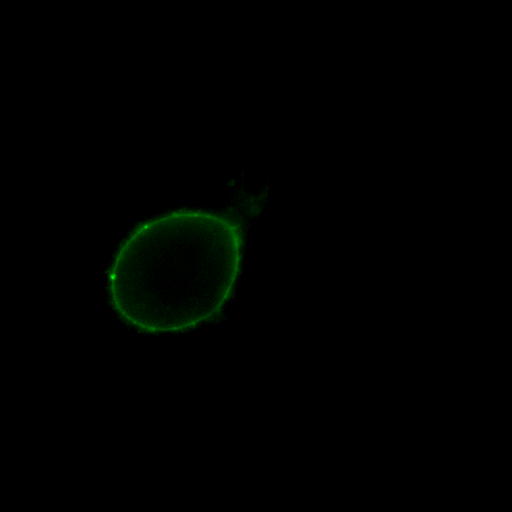

ナマズなどの魚卵には,ラムノース結合性レクチン(RBL)が含まれている.ナマズ卵由来RBL(SAL)は285アミノ酸から成り,95残基ずつの互いに相同性の高い3つのドメインから成る繰り返し配列を有するタンパク質で,バーキットリンパ腫細胞(RajiやDaudi)の糖脂質グロボトリアオシルセラミド(Gb3)に選択的に結合し,この細胞を短時間で縮小させる.しかし,細胞死は誘導しないユニークな性質を持っている.また,SALはこれらの細胞の細胞周期を停止させ,細胞増殖を阻害する働きもある.SALを利用して糖脂質糖鎖の情報伝達機構を明らかにできる可能性がある.